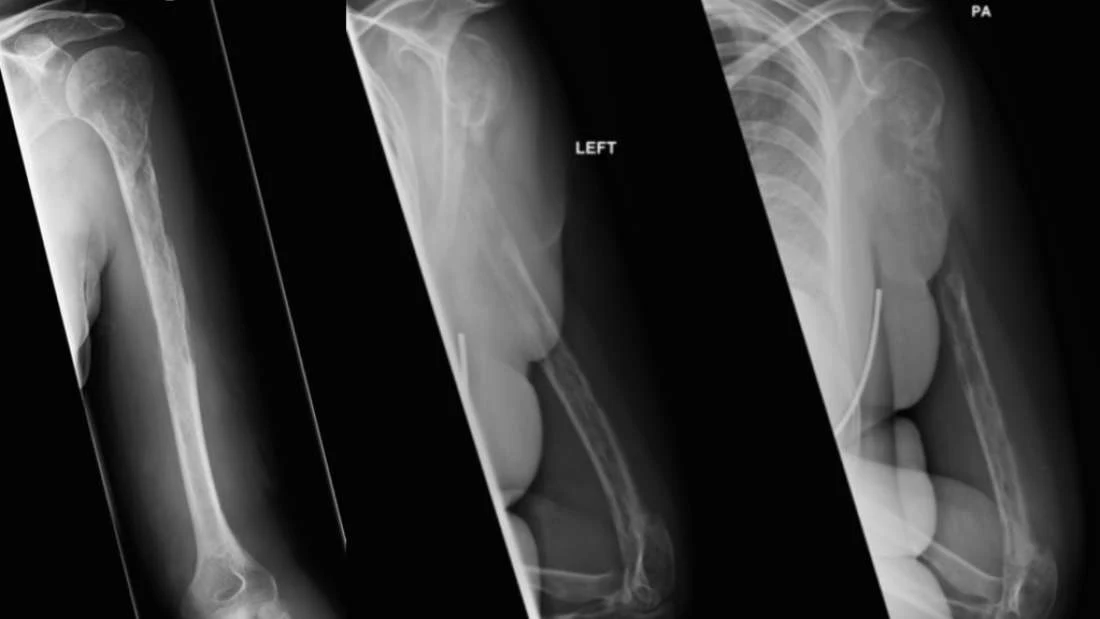

Kiedy pewna 44-letnia Szkotka odwiedziła lekarza z dolegliwościami bólowymi i brakiem możliwości ruchu lewego ramienia, nie wiadome było co jej jest. Zdjęcie rentgenowskie wykazało uszkodzenie kości ramiennej, które normalnie byłoby oznaką nowotworu, ale wyniki biopsji wykluczyły taką ewentualność. Dopiero 18 miesięcy później lekarze dokonali zaskakującego odkrycia o defragmentacji jej kości.U kobiety zdiagnozowano niezwykle rzadką chorobę Gorhama-Stouta (GSD) zwaną także "chorobą zanikających kości", w której pacjent stopniowo traci masę kostną. Przyczyny choroby i jej potencjalne leczenie są zagadką dla współczesnej medycyny. W wyniku osteolizy i nadmiernej proliferacji naczyń limfatycznych, kość jest progresywnie niszczona, gdyż wchłaniane są komórki ją budujące. Początkowo obraz choroby przypomina niejednolitą osteoporozę. Z biegiem czasu deformacje kostne są coraz bardziej widoczne, co utrudnia normalne funkcjonowanie.Medycyna do tej pory zna zaledwie 64 przypadki choroby Gorhama-Stouta, przy czym zaledwie osiem dotyczyło kości ramiennej. Pierwszy przypadek GSD zaobserwowano w 1838 r. Z powodu swojej rzadkości, choroba jest trudna do zdiagnozowania, a prognozy dotyczące stanu zdrowia nieprzewidywalne. Nie ma na nią lekarstwa. Działania podejmowane przez lekarzy mają na celu usuwanie niszczonych kości i podawanie bisfosfonianów, które zapobiegają utracie masy kostnej.Choroba Gorhama-Stouta może dotknąć jedną lub wiele kości na raz, w tym ramiona, nogi, szczękę czy miednicę. Gdy choroba dotknie kręgosłup lub podstawę czaszki, może doprowadzić do paraliżu. W niektórych przypadkach dochodzi do uszkodzenia klatki piersiowej, co może okazać się śmiertelne. Co najciekawsze, w niektórych przypadkach choroba spontanicznie znika równie szybko, jak się pojawiła. Rokowania pacjentki ze Szkocji nie są znane.